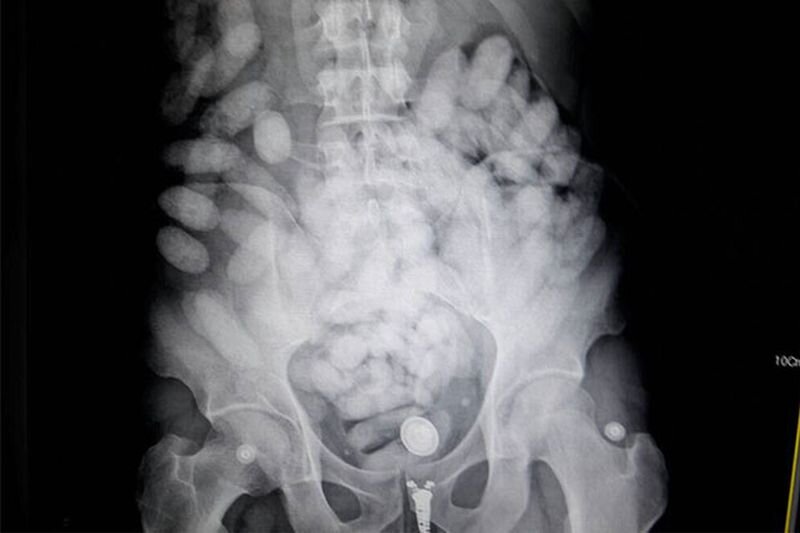

В московском аэропорте Внуково таможенники задержали девушку, перевозившую в желудке пол килограмма кокаина. Прилетевшая из Стамбула 23-х летняя россиянка пыталась доставить в Россию подобным образом, в общей сложности, 90 пакетиков с запрещённым веществом. Девушка признала вину, и рассказа о заказчике, с которым она должна была встретиться в одной из столичных гостиниц. Всего удалось изъять из оборота около полутора килограммов наркотиков. По факту содеянного возбуждены два уголовных дела. Понравилось? Подпишись!!! Читайте также:

В московском аэропорте Внуково таможенники задержали девушку, перевозившую в желудке пол килограмма кокаина. Прилетевшая из Стамбула 23-х летняя россиянка пыталась доставить в Россию подобным образом, в общей сложности, 90 пакетиков с запрещённым веществом.

Девушка признала вину, и рассказа о заказчике, с которым она должна была встретиться в одной из столичных гостиниц. Всего удалось изъять из оборота около полутора килограммов наркотиков. По факту содеянного возбуждены два уголовных дела.